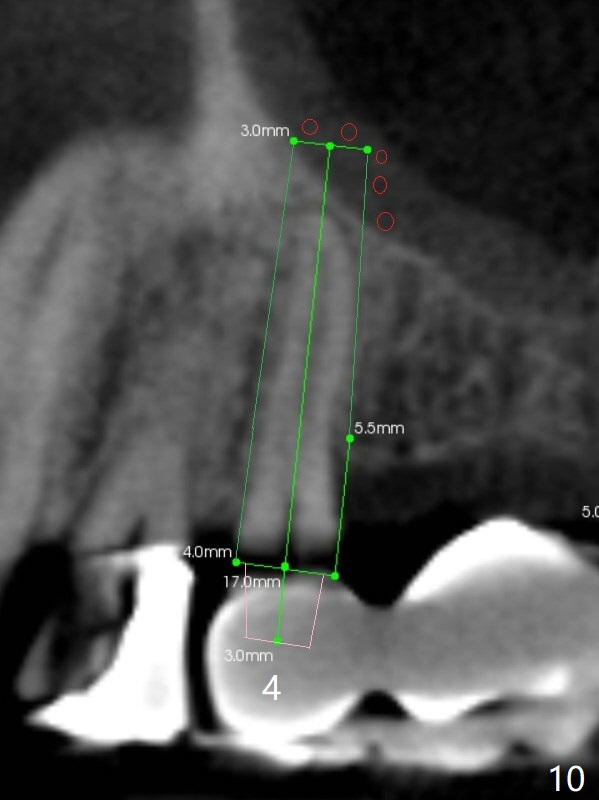

A 64-year-old man requests implant restoration after the upper FPD dislodges (Fig.1). The measurement of the septal height at #2 by PA (Fig.2) is not as precise as CBCT (Fig.11, taken 4 years earlier). There appears to be 2.8 mm bone apical to the tooth #4 (Fig.2); in contrast, the bone is more or less buccal and palatal to the root apex shown by CT (Fig.5). Furthermore CT more clearly shows apical lesions of the tooth #5 (Fig.3,4) than PA (Fig.2). In addition to pulpal test, RCT should be done for #5 prior to implant placement at #4.

After extraction of the tooth #4, osteotomy is initiated in the middle of the palatal slope (Fig.6), followed immediately by change in trajectory (Fig.7). The depth of the osteotomy is ~ 5 mm (Fig.8), followed by 2.8 mm round bur from Sinus Lift Master Kit. Press the burs palatally. Following Vanilla Graft (red circles), place a 3.5 or 4.0x17 mm dummy and final implants (Fig.3,9,10).